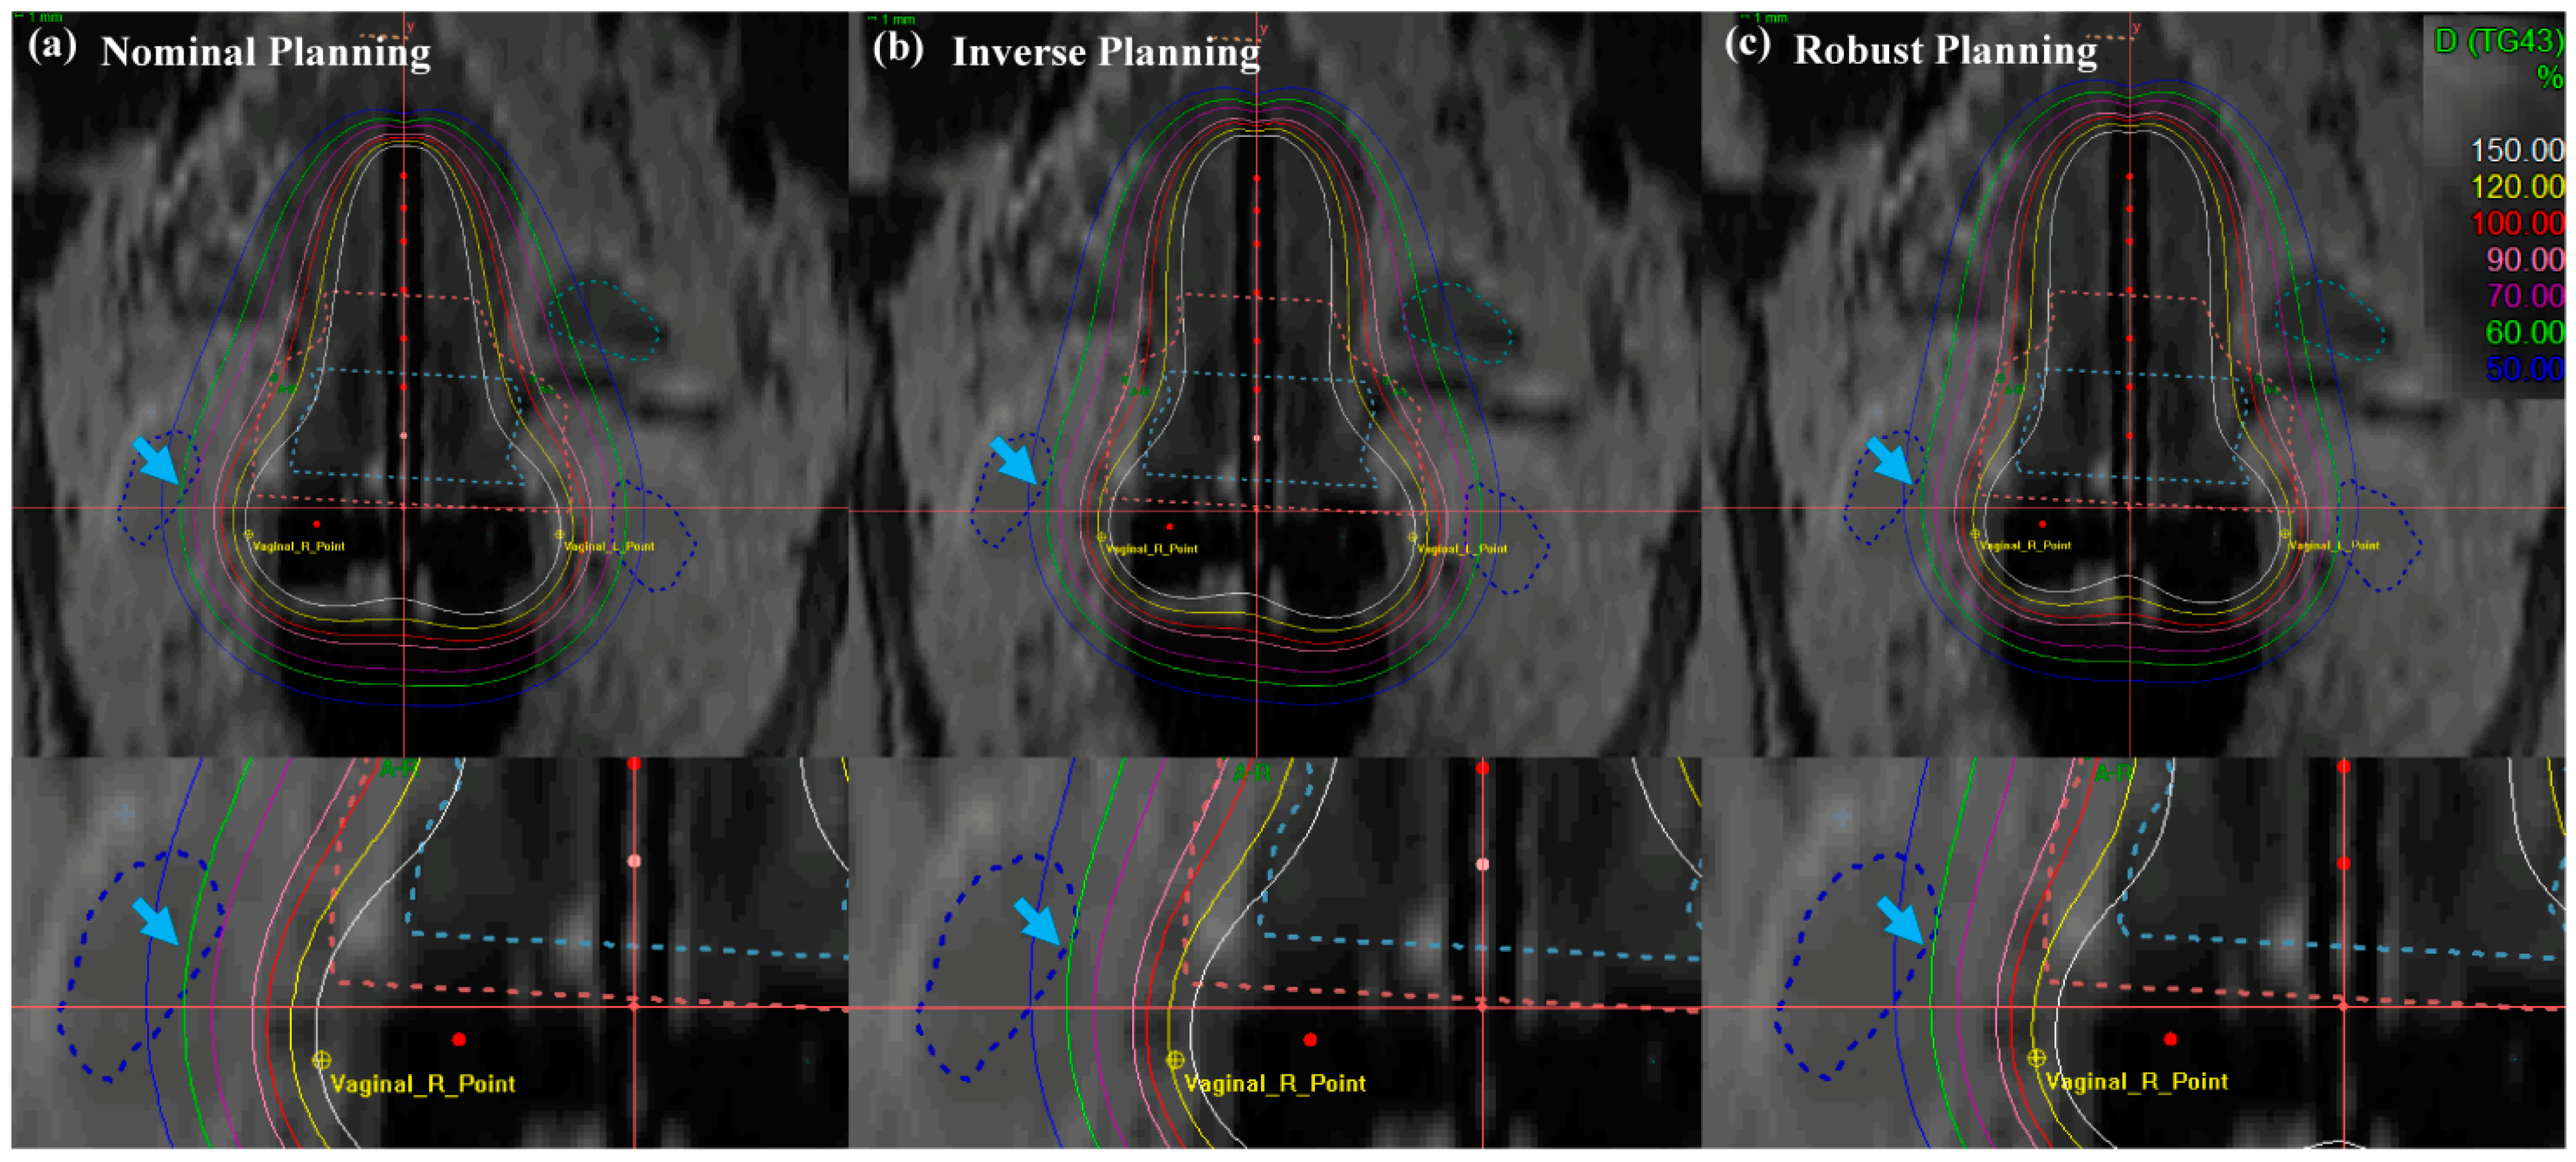

Figure 6 and Figure 7 illustrate the comparison of isodose lines calculated in the Oncentra Brachytherapy TPS of the nominal (manual) plan, inverse plan and robust plan for a cervical cancer patient. In all treatment plans, dwell times at each position for the desired target coverage were successfully encompassed based on EMBRACE protocol guidance. As shown in Figure 6, the bladder contour is encompassed by a minimum of percent isodose line in the robust planning while maintaining target-dose coverage and OAR sparing, rather than both coverage and sparing in the nominal and inverse planning.

Figure 6.

Isodose-line comparison of (a) nominal (manual) planning, (b) inverse planning, and (c) robust planning standard planning in EBRT brachytherapy boost treatment of cervical cancer: axial view. An EBRT total dose of 50.40 Gy was delivered in 28 fractions, and an ICR total dose of 30 Gy was delivered in 6 fractions using a TR applicator.

Figure 7.

Isodose-line comparison of (a) nominal (manual) planning, (b) inverse planning and (c) robust planning. Standard planning in EBRT brachytherapy boost treatment of cervical cancer: axial view. An EBRT total dose of 50.40 Gy was delivered in 28 fractions, and an ICR total dose of 30 Gy was delivered in 6 fractions using a TR applicator.

In Figure 7, the cervical brachytherapy plan showed the isodose line from a coronal view. Figure 7 demonstrated a reduced dose to the international commission on radiation units (ICRU) vaginal right (R), left (L) point, and sigmoid than nominal and inverse plans (blue arrow with a single arrowhead). Furthermore, the robust plan not only minimized the dose delivery of the ICRU vaginal R and L point, but it also minimized doses to the OAR, while maintaining coverage of uneven HR- and IR-CTV contours. The most distinct difference between the methods in the results for the target and OAR is that the robust optimization method improved the dose distribution and decreased the dose delivery uncertainty. Table 1 displays the numerical results corresponding to Figure 6 and Figure 7.